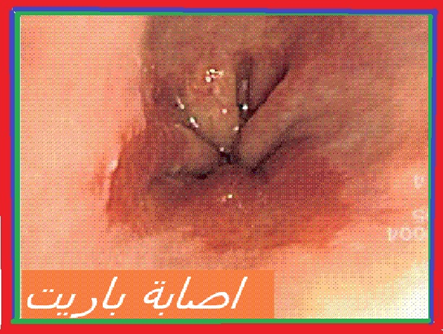

في حالة الإصابة بحالة ا م م المصحوبة بالأعراض السريرية بجانب العلامات النموذجية و علامة الحذر (السن الذي يفوق 50 سنة أو فقدان وزن الجسم أو علامة النزيف أو عسر الهضم) . وبالتالي فالتنظير الباطني الطبيعي تحت غلاف العلاج بأدوية م م ب لا تستثني الإصابة بالتهاب المريء يعد سبب بروز الأعراض السريرية ولذلك يتحتم بقدر المستطاع اللجوء الى انجاز التنظير الباطني في غياب تناول م م ب كلما برز شك في الإصابة بحالة ا م م

ضمن المصابين الذين تفوق أعمارهم 65 سنة الذين يتلقون العلاج بواسطة أدوية م م ب حضت نسبة 8 % منهم بفحص التنظير الباطني للمعدة المريء والاثني عشر. يوصي بإنجاز هذا الفحص كلما تم الشك في الإصابة بحالة ا م م . و بالرغم الحالة التي يبدو خلالها التنظير طبيعيا بالنسبة لنصف المصابين الذين يعانون من أعراض ا م م فان التنظير يتيح تأكيد وجود ا م م في حالة تشخيص إصابات المريء و خاصة تشخيص آفات أخرى مثل البطانة المخاطية باريت أو تشخيص ورم . يعتقد اذن انجاز هذا الفحص من الأهمية بمكان. وخلاصة حينما يدور الحديث حول العلاج الطويل المدى لكي لا نتجاهل الإصابات التي تتطلب أخذ الموقف الخاص و الحفاض على المراقبة

خلاصة القول : يعتقد من الأهمية بمكان إعادة التقييم الدوري لوصف أدوية م م ب تجنبا لصيانة العلاج في غياب حالة ا م م الى . حد الساعة لم يتم اللجوء لعلاج المصبين بأدوية م م ب بالنسبة للمصابين الذين يعانون من الغشاء المخاطي لبرت (32) دون حالة ا م م أو التهاب المريء. غير أن دراسة طبية جديدة أثبتت بجانب ذلك أن التأثير أكثر أهمية بالنسبة للجرعات المضاعفة مقارنة مع الجرعات البسيطة اما اسبيرين بمنفردها تعتقد متجردة من المفعول الأمر الذي يدعو الى مراجعة الوصية حول عدم التوصية بعلاج المصابين المجردين من الأعراض السريرة و الذين يعانون من الغشاء المخاطي لباريت . نحن في تطلع مستمر لدراسات جديدة لعلها تؤكد فعالية ادوية م م ب .